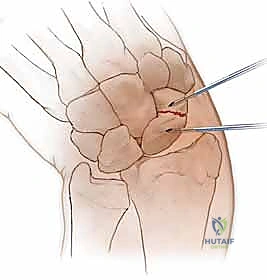

1. المدخل البطني (Volar Approach): من جهة راحة اليد. يُستخدم عادة لكسور منطقة الخصر (المنتصف).

الخطوة 2: تحديد مسار المسمار بدقة (Guidewire Placement)

هذه هي الخطوة الأكثر أهمية والتي تتطلب مهارة استثنائية. يقوم د. هطيف بعمل شق صغير جداً (بضعة مليمترات). باستخدام جهاز الأشعة، يقوم بإدخال سلك معدني